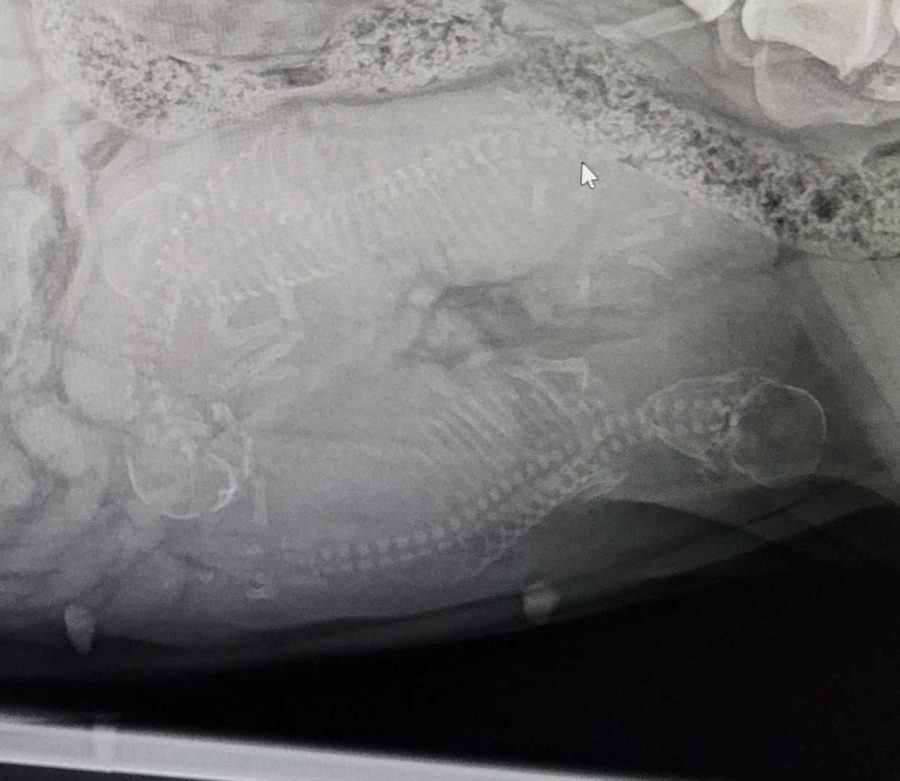

Wir habern beim röntgen 3 Welpen gesichtet. Greta ist für ca. 12.4.23

ausgezählt.